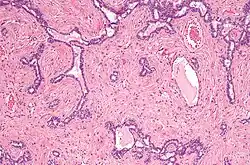

Micrografia do rete testis envolvida por seminoma. Mancha de H&E.

Micrografia do rete testis envolvida por seminoma. Mancha de H&E. -